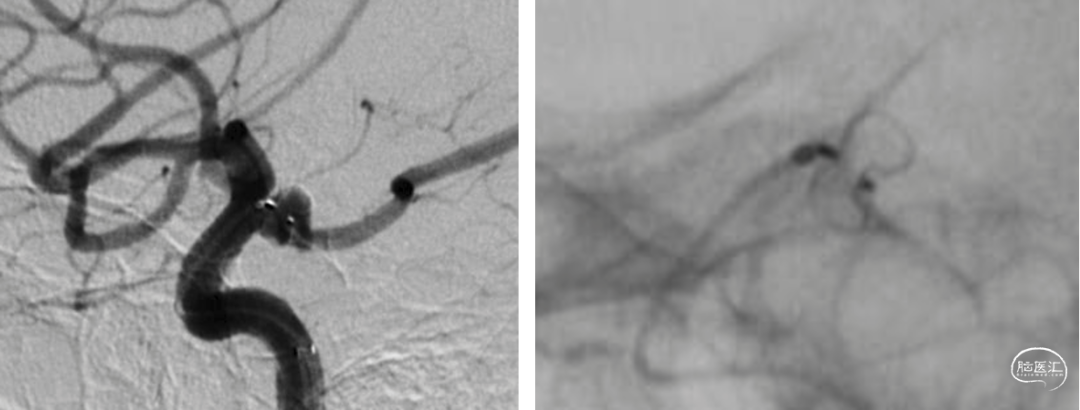

DSA

平均宽度(4.5+3.8)=4.2mm,最小深度7.5mm,选择SL5x3

微导管到位动脉瘤腔

通过VIA17释放web

造影可见造影剂滞留

手推造影-推挤-造影

解脱web

术后正侧位造影

术后CBCT